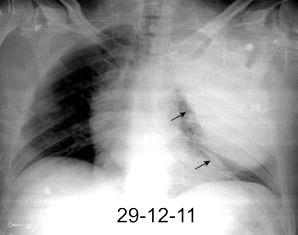

29. DERRAME PLEURAL IZQUIERDO. SÍND. DE AFECTACIÓN POSTCARDIACA

Síndrome de afectación postcardiaca (postcardiac injury)

Post infarto 1-7 % (Dressler)

Trauma cerrado Implantación marcapasos

Cirugía cardiaca. 17-31% (Post.pericardiotomía)

3707 pacientes 29 Derrames (0,78%) > de 25% del hemitórax

Todas menos 2 Izdos.

Angioplastia

By-pass coronario 21-10-03